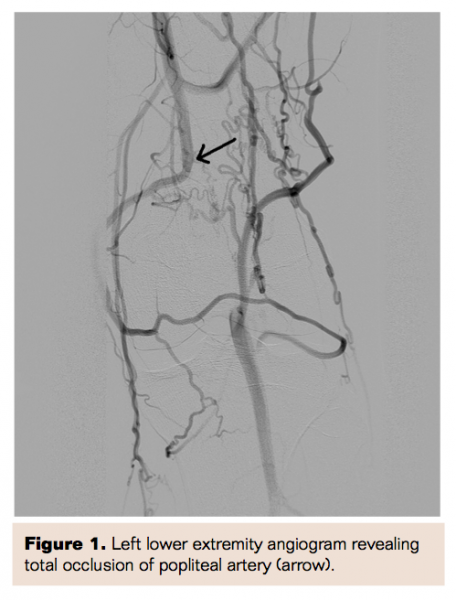

A 17-year-old white male was referred to the vascular surgery clinic after being seen by orthopedic surgery for disabling claudication in his left lower extremity of 2 months duration with significant worsening over the past week. The patient had four compartment fasciotomies performed by orthopedic surgery prior to referral for concern for exertional compartment syndrome. Upon evaluation, the patient did not have any prior significant past medical or surgical history. On physical examination, no pedal or popliteal pulses were felt; the patient had intact motor and sensory function of his left lower extremity. The patient underwent angiography, which revealed complete occlusion of the left popliteal artery (Figure 1). The patient underwent a posterior approach for exposure of the popliteal fossa. The popliteal artery was found to be coursing medial to the medial head of the gastrocnemius muscle medially. Proximal and distal control of the artery was obtained, the artery was divided, and an interposition lesser saphenous vein graft was used to reestablish flow. The patient had an uneventful hospital course. Upon 1-year follow-up, the patient was asymptomatic with palpable pedal pulses.